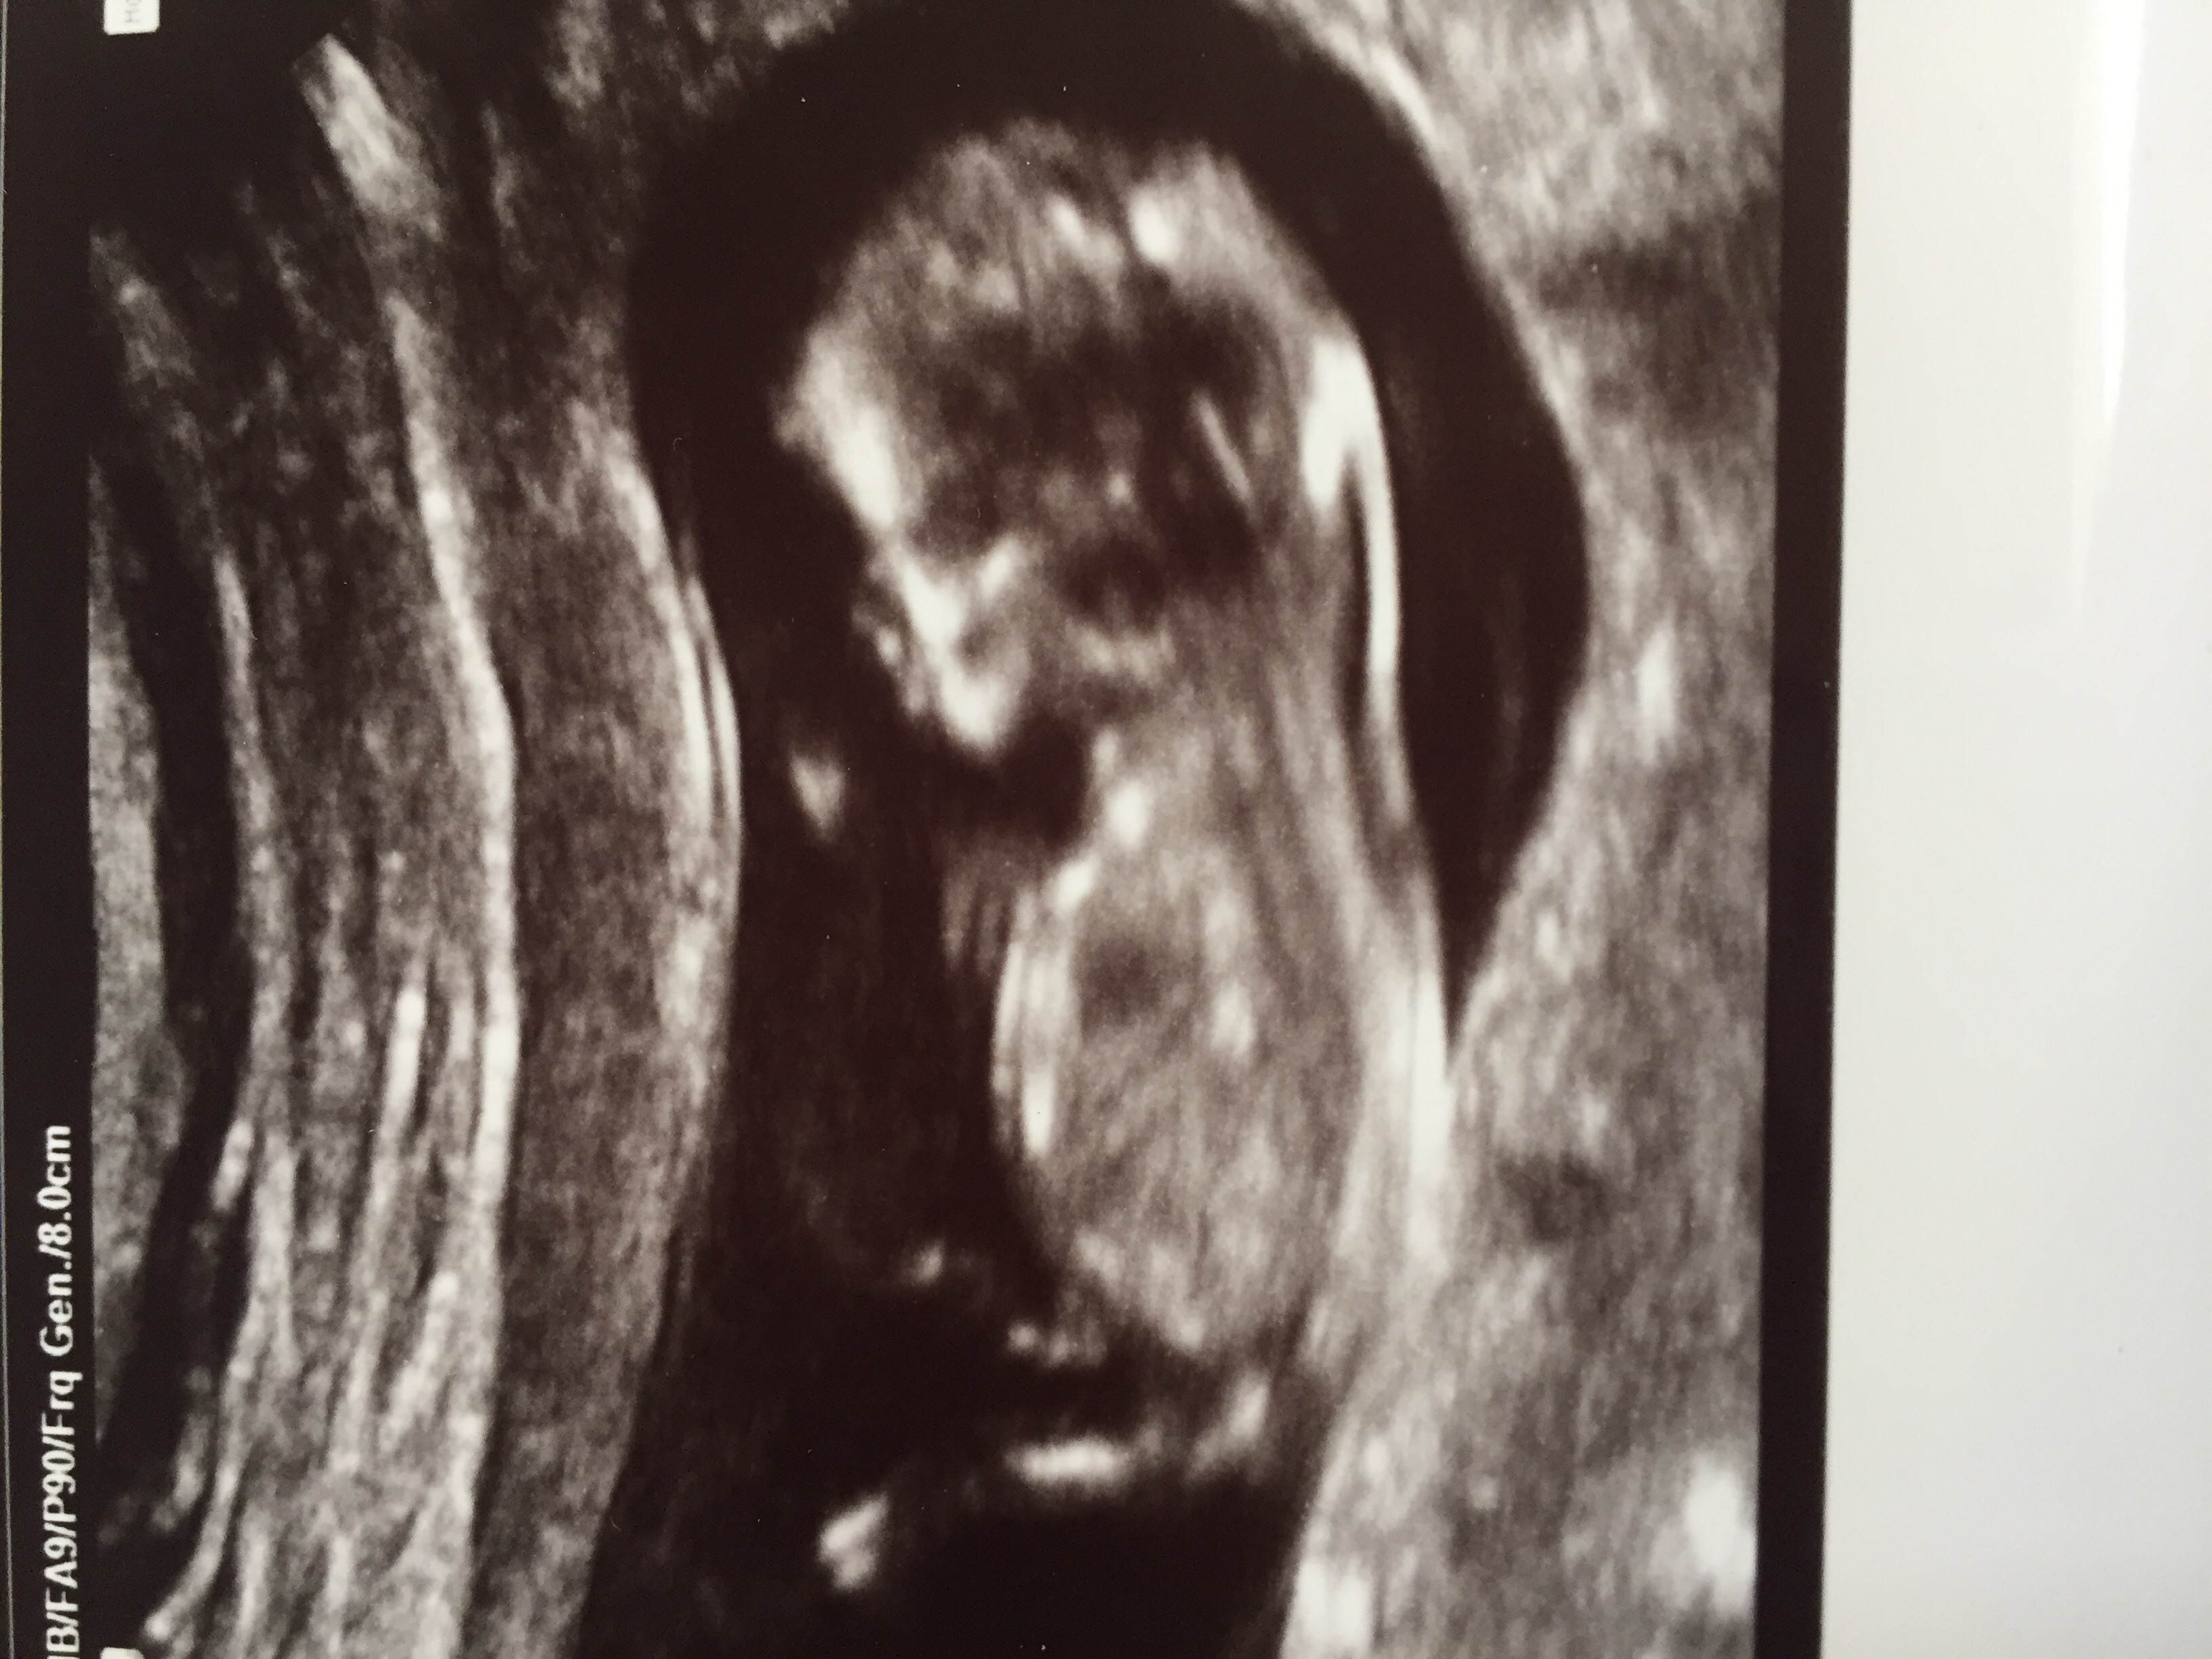

Very delayed but at my 8 week appointment they did an u/s and I'm willing to bet I walked away with the ugliest u/s picture of the bunch. (She only did 3d to try and get a better measurement). We did get a "normal" one too. Gummy bear versus melted gummy bear as she put it.